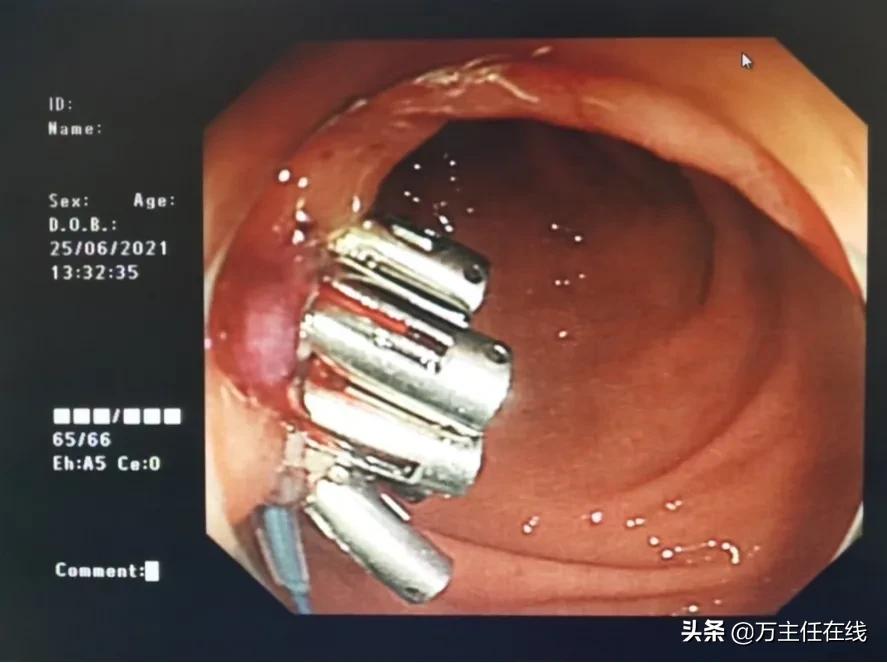

图表 2万荣医生团队正在手术中

图表 3成功切除肝囊肿

图表 4完成手术,缝合胃窦切口

在完善术前的相关检查后,消化内科万荣团队为陈女士进行了手术。手术进行非常顺利,成功为患者完成了双侧肝囊肿切除术。陈女士醒来后惊讶的发现自己竟无任何腹痛不适,看着自己完美无瑕的肚子,正如同手术路径所展示的那样,陈女士也在手术结束后露出了开心的笑容。